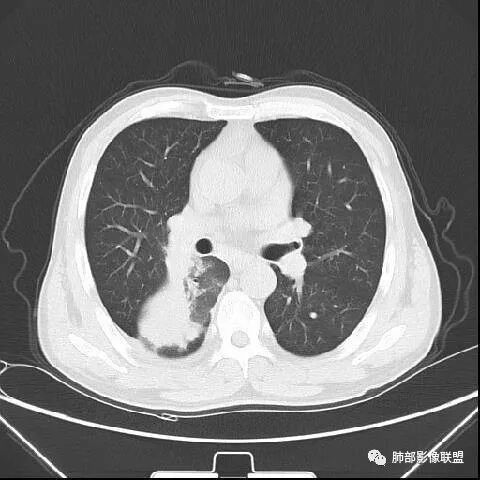

南边:紧贴着斜裂过来的一个病灶,它的特点是:外围大,内带小。它整个下叶背段体积与对侧相比稍微缩小一点,但是缩小地不是很厉害。外支朝前下走了,仔细看血管,肺动脉走行自然,直达远端。远端实变区是肉芽肿成分,稍微有一点低密度,没有明显坏死,稍微有一点点坏死。而且附近有很多卫星灶,附近很多斑片影,有一些明显有气道壁增厚,细支气管炎的特点,还有就是下叶其他段很多斑片状影。换个角度,第一如果是肺癌,刚才看到PET-CT提示肺癌伴阻塞性肺炎,这个是不符合的。第二如果是肺癌阻塞性肺炎,近端血管肺动脉走行不会那么自然集聚的,这个是不符合的。理由是:如果这个病灶是肺癌,那么明显属于中央型肺癌,中央型肺癌的特点是近端大,远端小,近端是一个肿块,远端阻塞,远端阻塞是阻塞性炎症或者不张,它应该体积缩小,斑片状实变,不会这么密实。刚才有老师提到支气管,这个片有缺陷的地方,给的图像好像那层,如果把其他图像拿开再重叠一下。

鉴别诊断:肺炎性肺癌,胸膜下起源,外围大,局部占位效应,有膨隆有收缩,这个不太支持。支气管走行里面没有看到支气管进入很自然堵塞的粘液栓的特点。附近这些磨玻璃影,它的磨玻璃影要么边界清楚,要么由内朝外蔓延的,而不是沿着支气管束蔓延的。而且附近斑片状影,有些似乎有结节感,但是大部分不是,它不是我们常见的磨玻璃样结节,有些有,导致像腺泡样结节那种椭圆的沿着血管束分布的,我会把肺炎型肺癌放在待排。

右肺下叶背断肿块,外围大,内带相对狭长         远端有膨隆,边缘模糊、凹凸不平         血管走形自然,病灶近端支气管通畅,沿支气管树蔓延         周边有多发病灶,多为磨玻璃密度且边界不清。